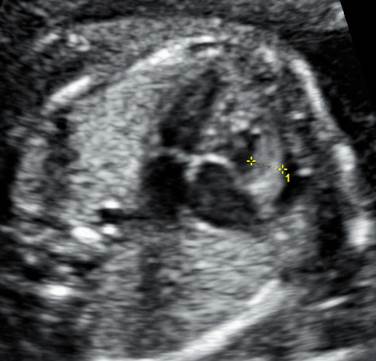

Вопрос 4

22 недели. Какие изменения видим? Какое обследование порекомендуем?

Ответ на вопрос 4

- Аномальная форма головки, лиссэнцефалия, возможно формирование краниосиностоза.

- Микрогнатия, гипертелоризм.

- Полидактилия.

- Брюшная лимфангиома.

- Рекомендуем ХММА.

- В данном случае выявлена клинически значимая делеция Х хромосомы.